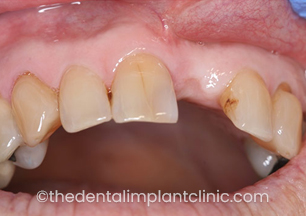

Missing upper right central incisor tooth (UR1) due to trauma

Missing UR1 with bone loss due to trauma

Procedures staged: [1] Block bone graft allowing the bone to regenerate for 9 months [2] Implant placement UR1